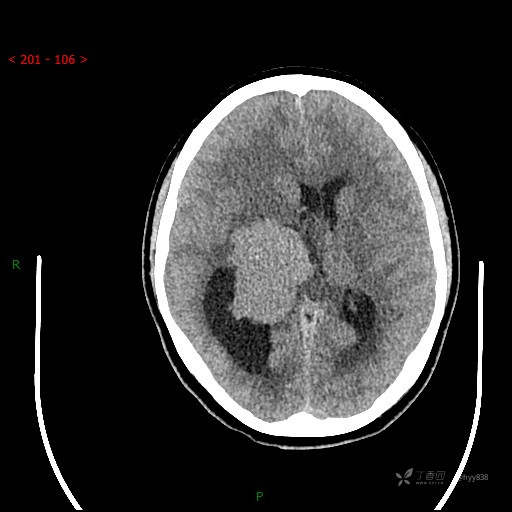

简要病史:患者于1月前无明显诱因出现视物模糊,无明显头痛头晕,无恶心呕吐,无昏迷,无肢体偏瘫等症状,就诊于当地医院头部CT考虑:右侧丘脑、脑室占位。予以对症处置后家属为求进一步诊治来我科,以“颅内占位”收入院。 起病以来,精神、饮食、睡眠欠佳,大小便正常,体力下降,体重无明显变化。

临床诊断:脑室占位

颅脑CT平扫